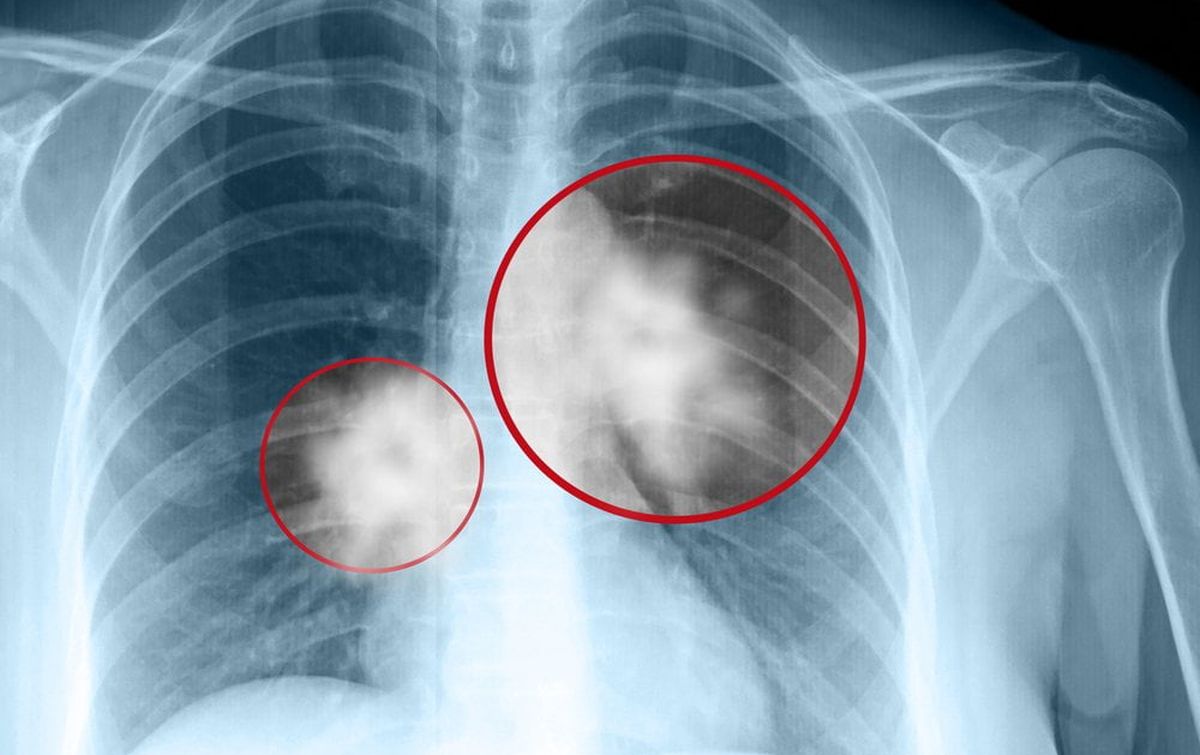

După șase săptămâni, a decis să meargă totuși la spital, iar medicii i-au dat o veste devastatoare. O radiografie a arătat că bărbatul avea mai multe mase suspecte în ambii plămâni.

O radiografie toracică a relevat o masă mare în plămânul drept și „mai multe mase mici” în ambii plămâni, care erau specifice pentru cancer, a spus Kube. Jason a fost internat pentru teste suplimentare, iar diagnosticul a fost confirmat.